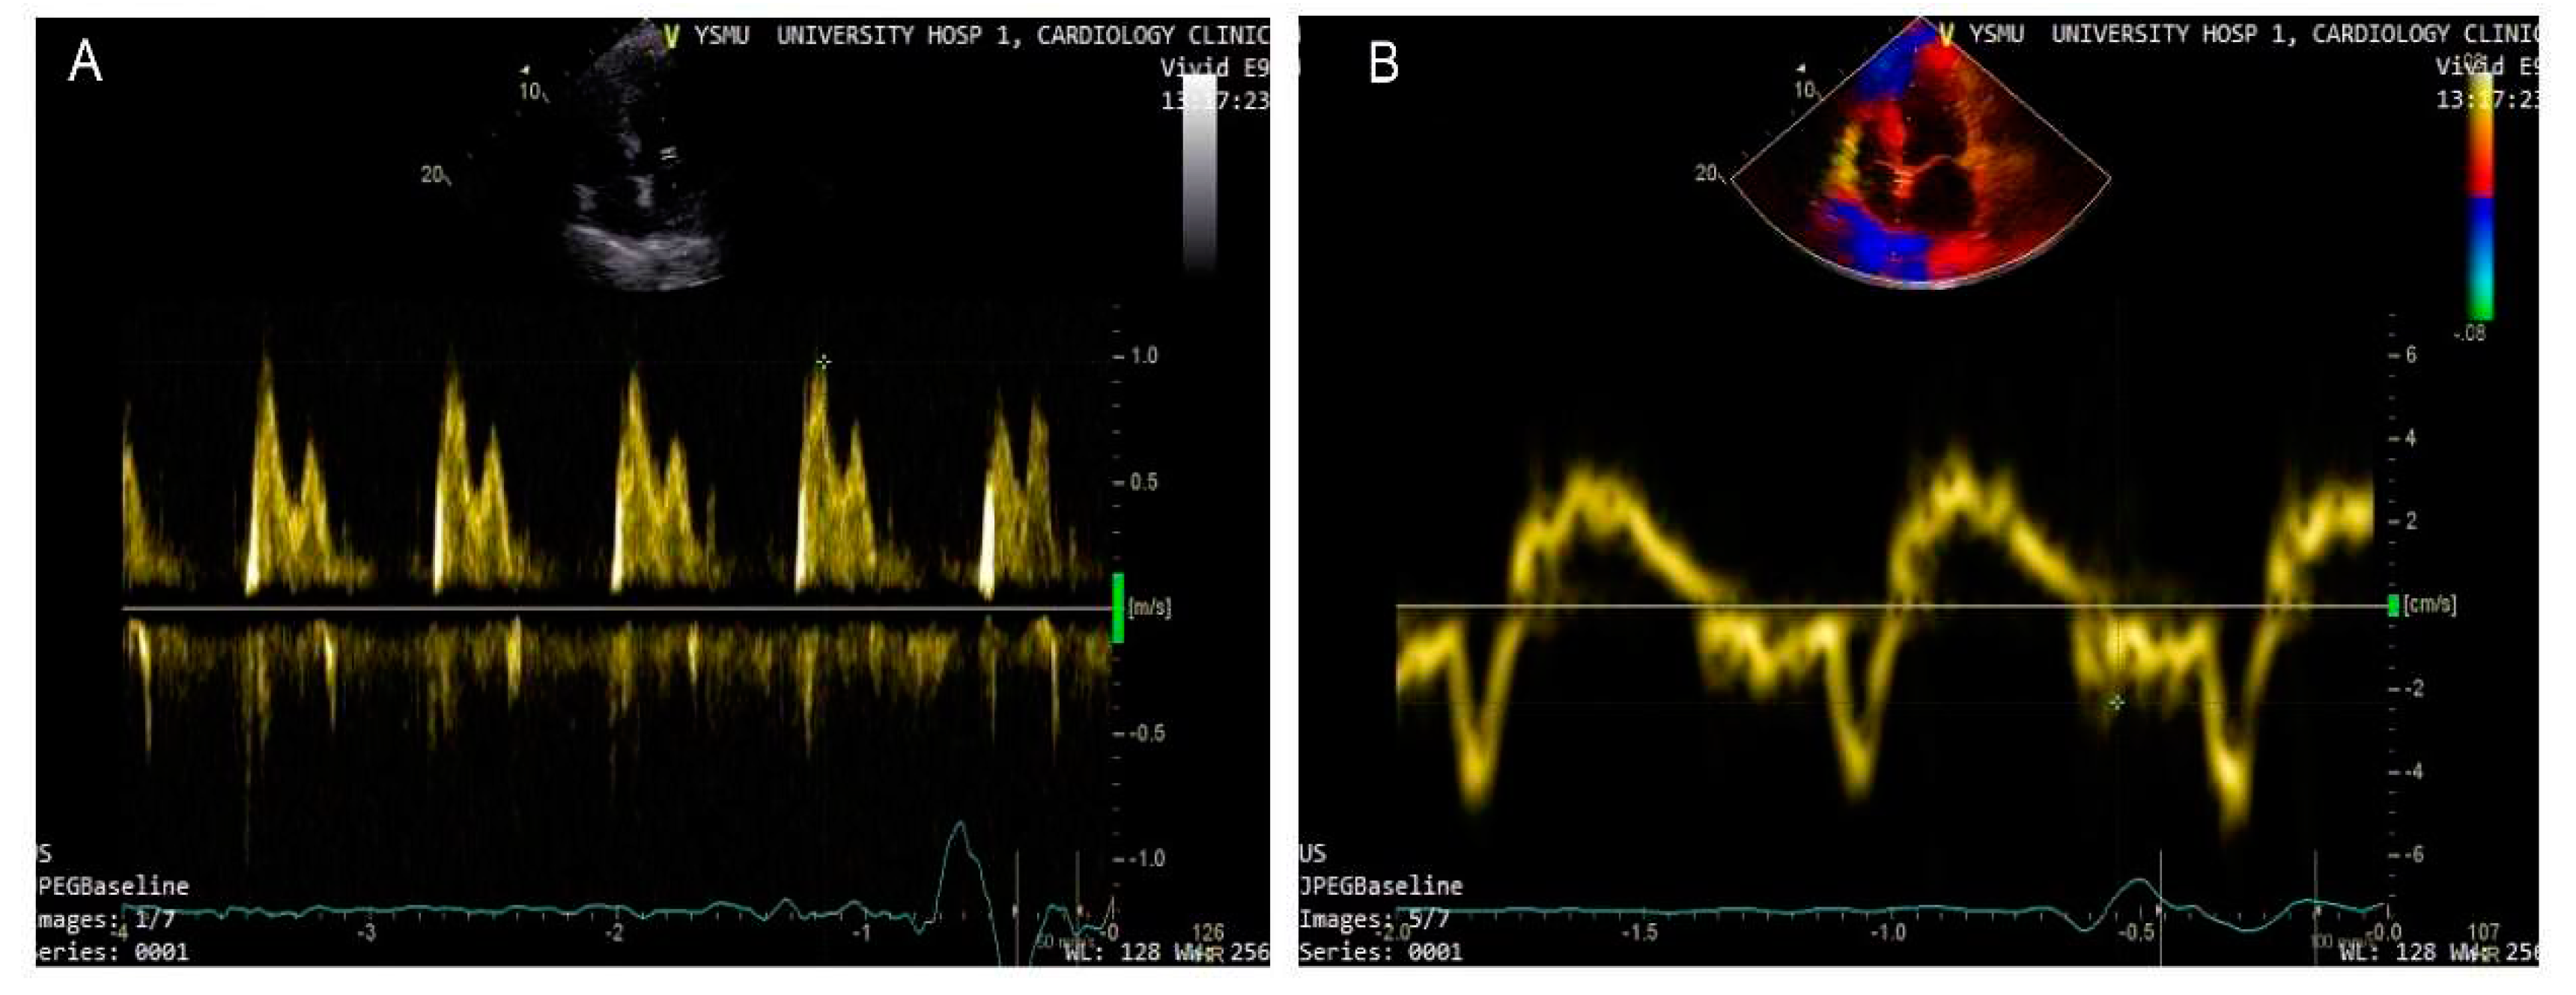

- Nagueh, S.F.; Smiseth, O.A.; Appleton, C.P.; et al. Recommendations for the Evaluation of Left Ventricular Diastolic Function by Echocardiography : An Update from the American Society of Echocardiography and the European Association of Cardiovascular Imaging. J Am Soc Echocardiogr. 2016, 29, 277–314. [Google Scholar] [CrossRef] [PubMed]

- Ommen, S.R.; Nishimura, R.A.; Appleton, C.P.; et al. Clinical utility of Doppler echocardiography and tissue Doppler imaging in the estimation of left ventricular filling pressures: A comparative simultaneous Doppler-catheterization study. Circulation. 2000, 102, 1788–1794. [Google Scholar] [CrossRef] [PubMed]

- Park, J.H.; Marwick, T.H. Use and Limitations of E/e' to Assess Left Ventricular Filling Pressure by Echocardiography. J Cardiovasc Ultrasound. 2011, 19, 169–173. [Google Scholar] [CrossRef]

- Lancellotti, P.; Galderisi, M.; Edvardsen, T.; et al. Echo-Doppler estimation of left ventricular filling pressure: results of the multicentre EACVI Euro-Filling study. Eur Heart J Cardiovasc Imaging. 2017, 18, 961–968. [Google Scholar] [CrossRef]

- Jones, R.; Varian, F.; Alabed, S.; et al. Meta-analysis of echocardiographic quantification of left ventricular filling pressure. ESC Heart Fail. 2021, 8, 566–576. [Google Scholar] [CrossRef]